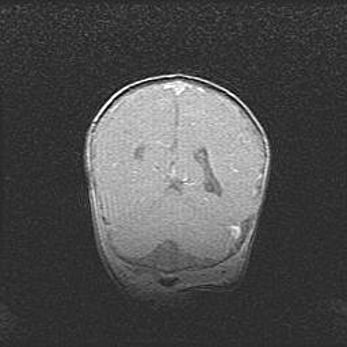

Аномалия Денди-Уокера. Признаки гипоплазии мозолистого тела.

Возраст: 5 месяцев 3 дня

Вес: 5550 г

Пол: мужской

Окружность головы: 39 см

Срок гестации: 40 недель

Аномалия Денди-Уокера – это порок развития головного мозга, для которого характерна триада симптомов: гипотрофия или аплазия червя мозжечка и/или полушарий мозжечка, расширение четвёртого желудочка с формированием ликворной кисты задней черепной ямки, гипертензионная гидроцефалия различной степени.

Гипоплазия мозолистого тела относится к дефектам внутриутробного этапа развития мозговой ткани, возникающим в процессе закладки структур головного мозга, что происходит на начальных этапах развития эмбриона.